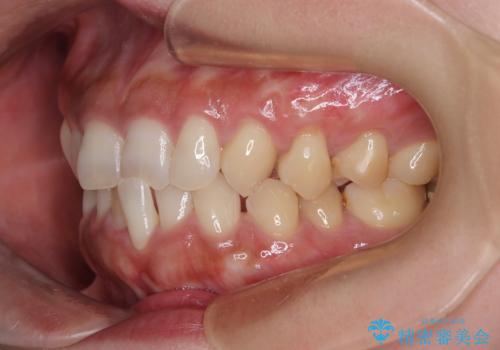

- 食いしばりと強いブラッシングにより、上顎小臼歯2本に知覚過敏を感じるようになったとのことで来院された患者様です。

歯肉退縮により歯根部が露出し、冷たい飲み物に痛みを感じる状態でした。

歯肉が薄い状態であったため、歯肉退縮が起こりやすいと判断された患者様でした。

根面被覆を達成するとともに、歯肉の厚みを増すことで、今後歯肉退縮を起こしにくくするよう配慮した処置としました。